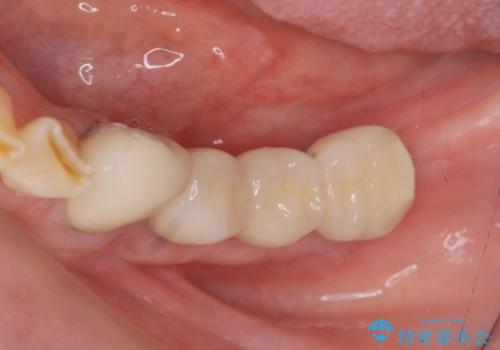

- 80万円(インプラント×2・アバットメント×2・ジルコニアクラウン×3)費用は治療当時の料金となります